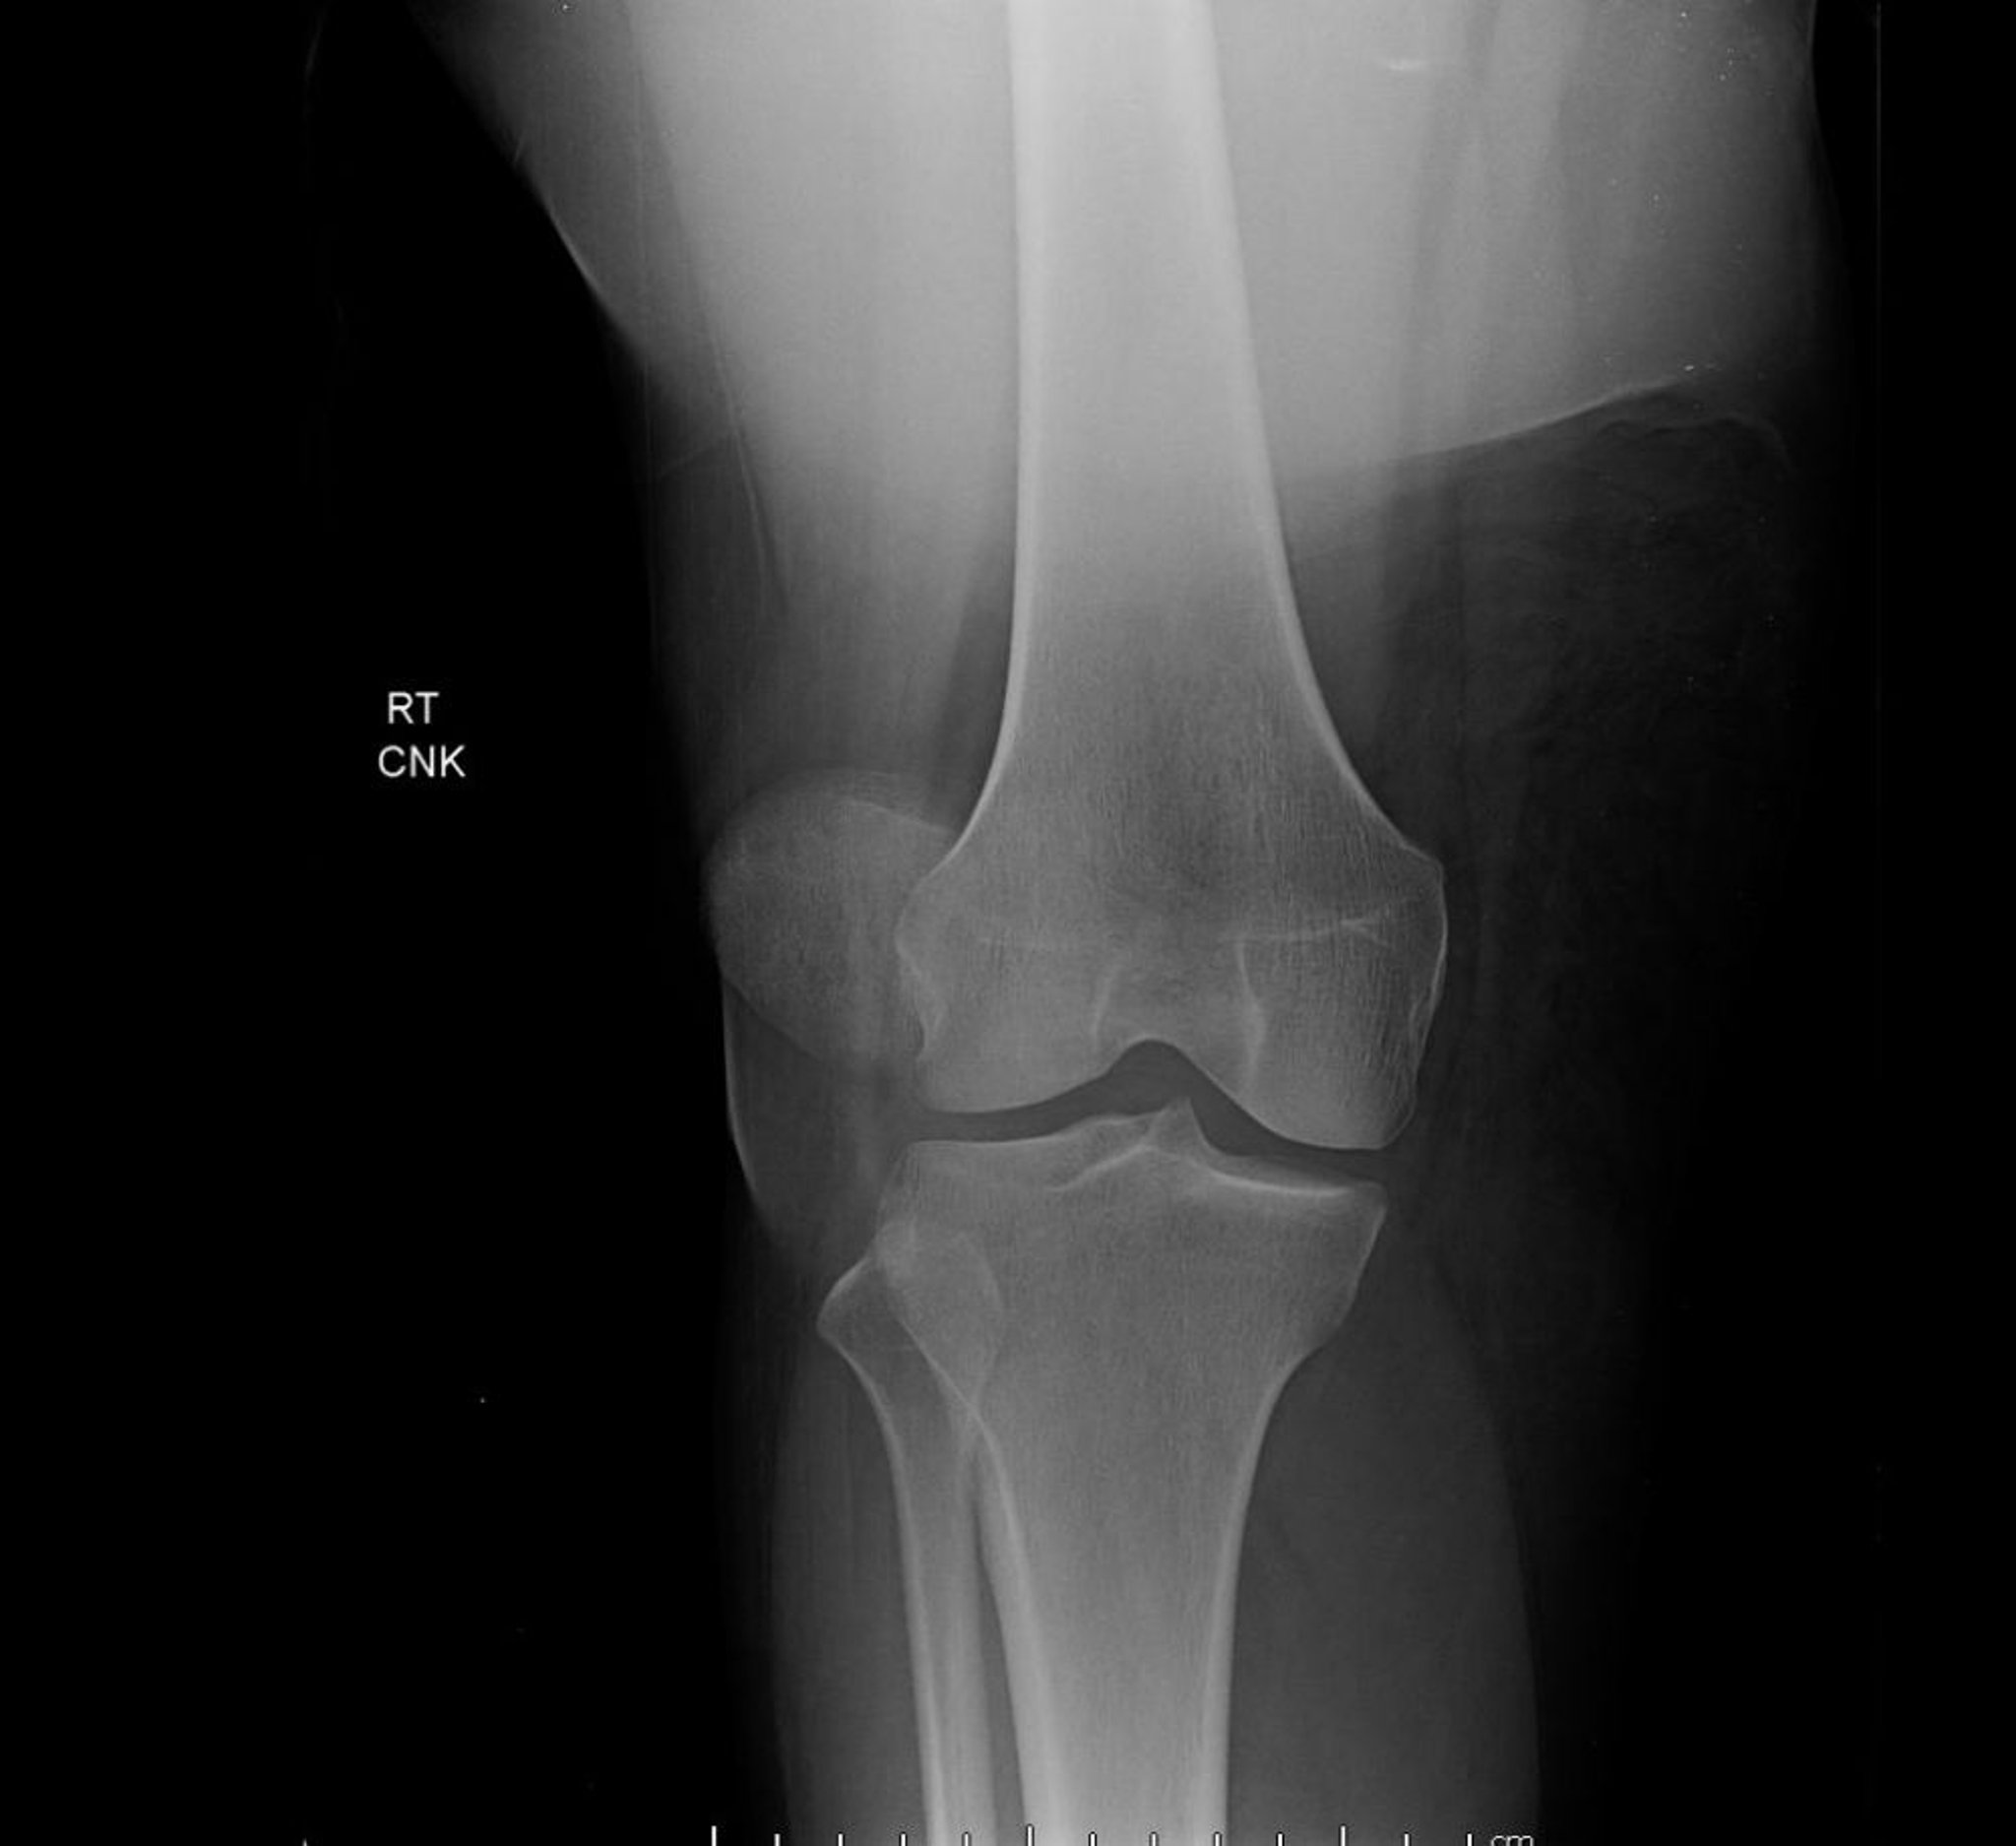

Luxation de la rotule (radiographie)

Cette vue antéropostérieure du genou montre une luxation rotulienne, caractérisée par un déplacement latéral extrême de la rotule, en dehors de son emplacement normal entre les condyles fémoraux.

Image courtoisie de Danielle Campagne, MD.